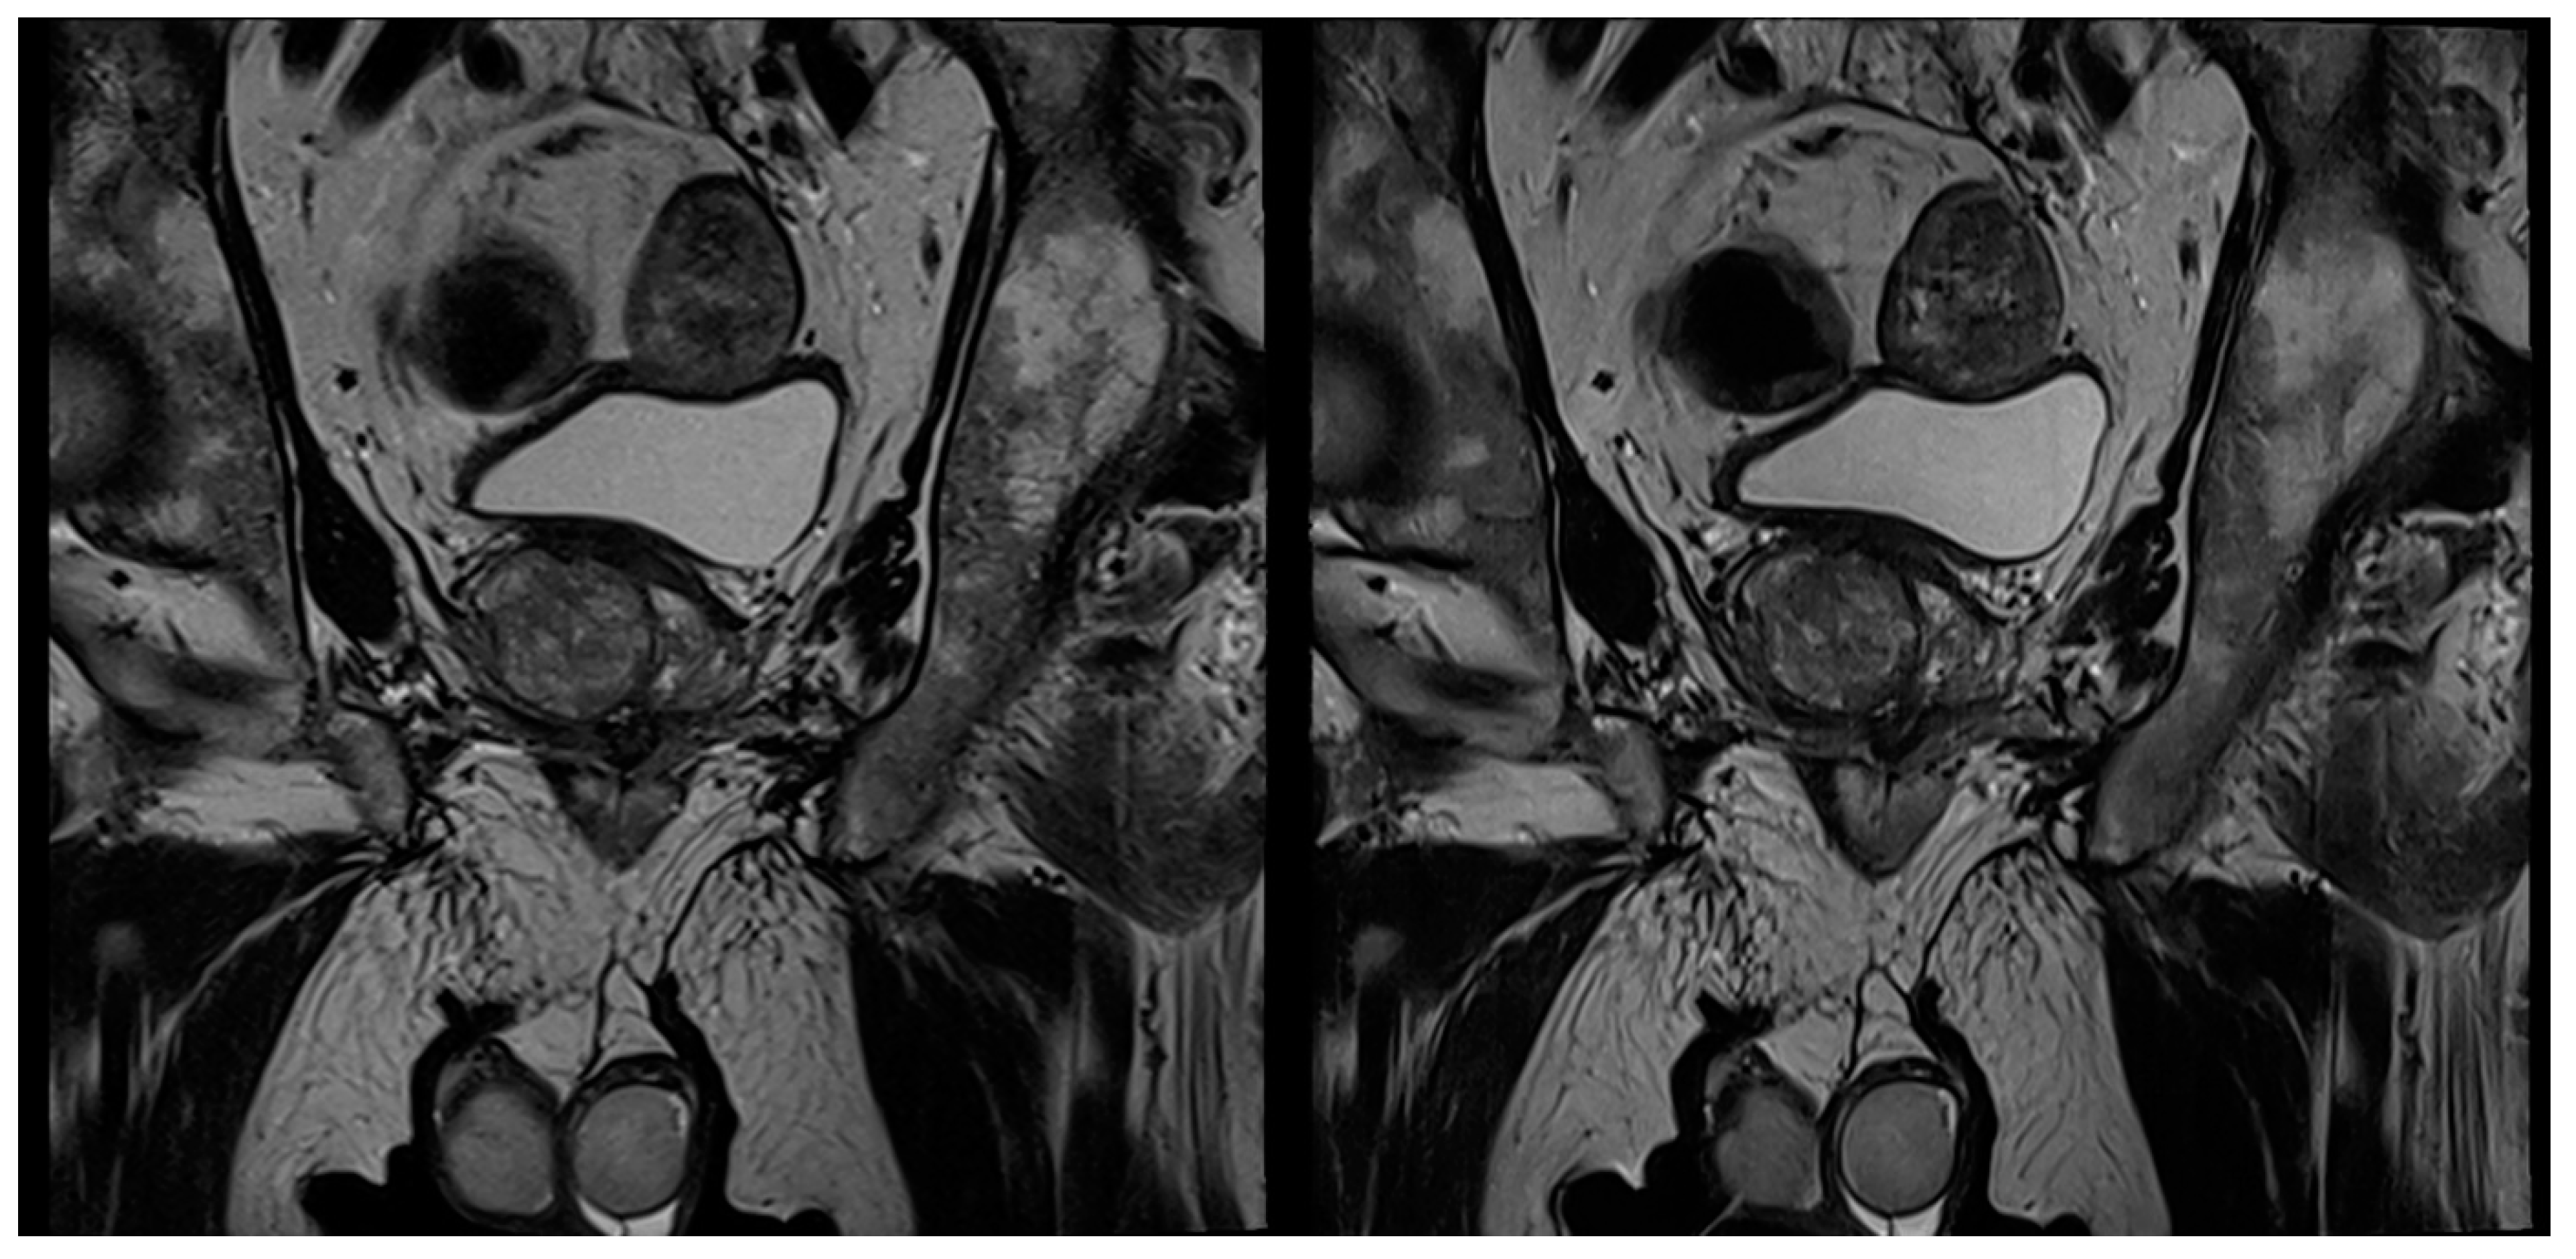

Figure 2. A 59-year-old male patient with suspicion of prostate cancer. Example of axial standard T2-weighted TSE imaging (T2S) on the top left-hand side and deep learning–reconstructed (T2DLR) imaging on the top right-hand side. The bottom row shows apparent diffusion coefficient (ADC) map on the left-hand side and dynamic contrast-enhanced (DCE) imaging on the right-hand side. PI-RADS 5 lesion in the transition zone was found by both readers in both sequences. Motion artifacts are especially reduced in T2DLR demonstrating the advantages of reduced acquisition time.